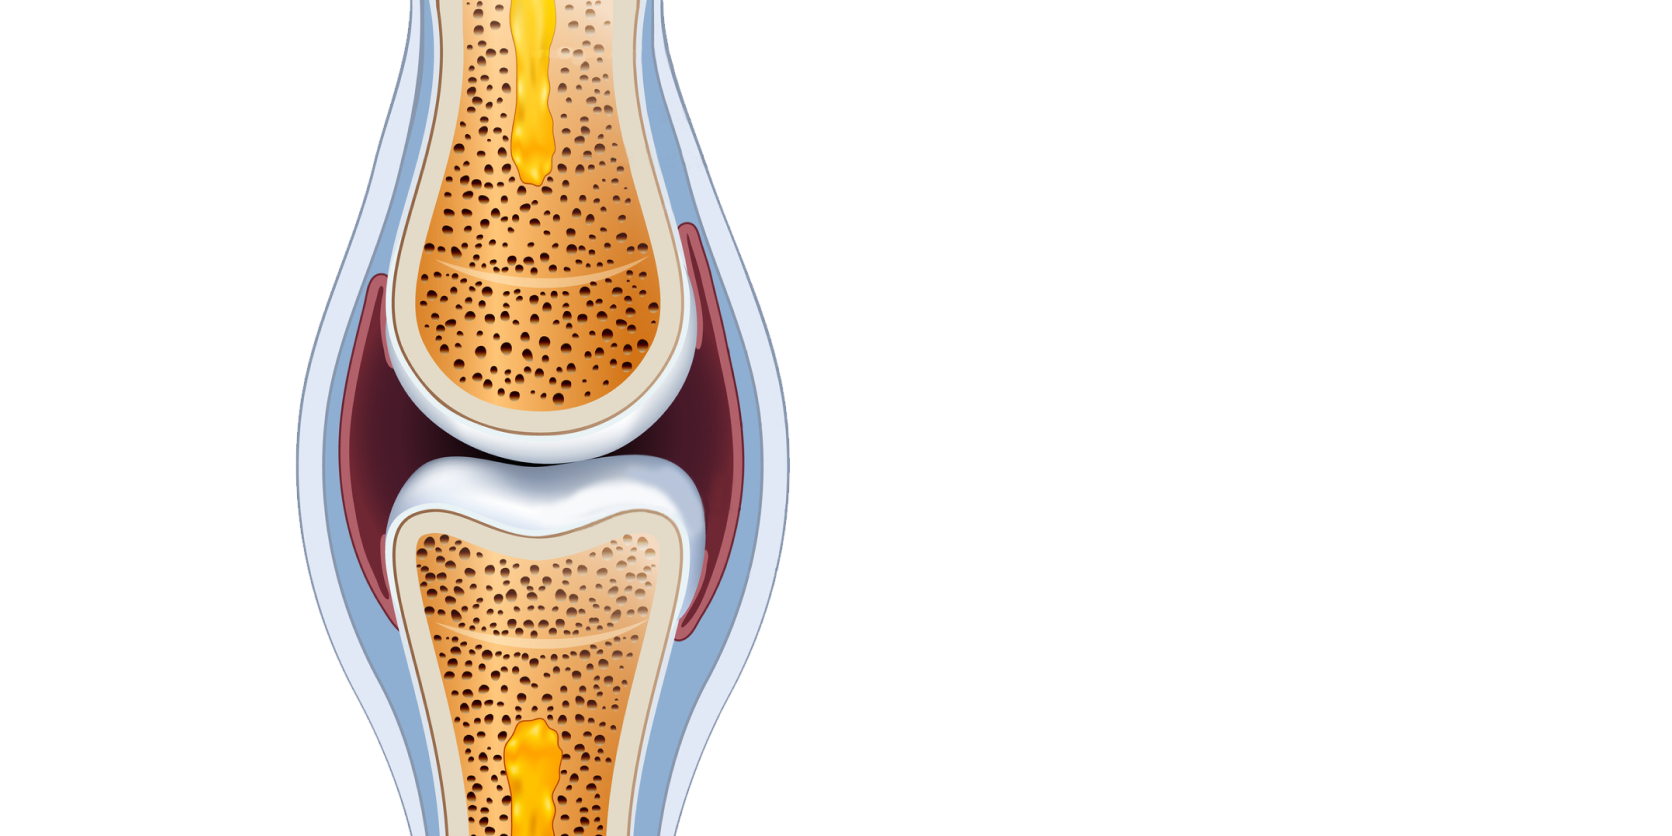

Hyaluronic Acid 150 mg; Chondroitin Sulfate 300 mg: Vitamin E 15 mg; other ingredients.

Chondroitin Sulfate

Hyaluronic Acid

150 mg | - |